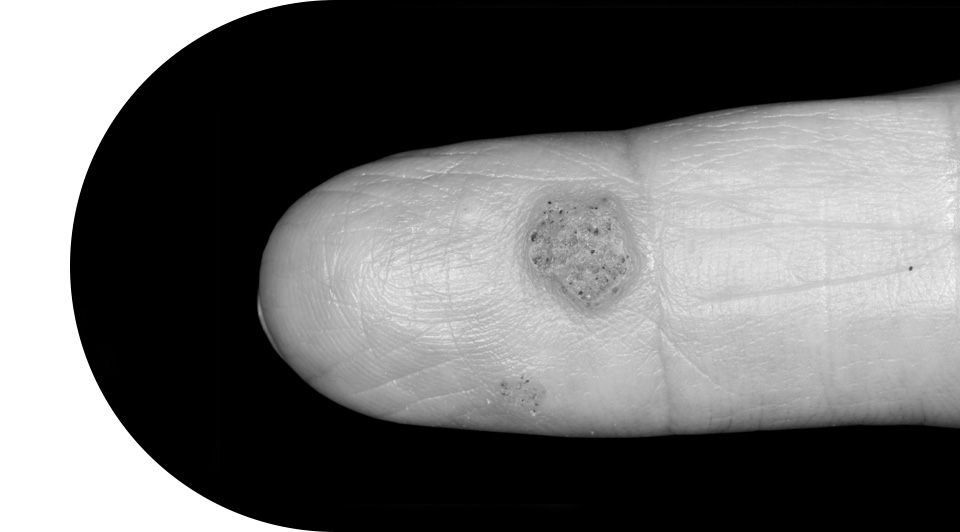

번지기 쉬운 사마귀/티눈

사마귀는 유두종 바이러스(HPV)에 의해 나타나며

전염성이 있어 빠른 치료가 필요합니다.

티눈은 물리적인 자극 마찰로 발생하는 질환으로

심지가 있어 압력이 가해지면 통증을 유발합니다.